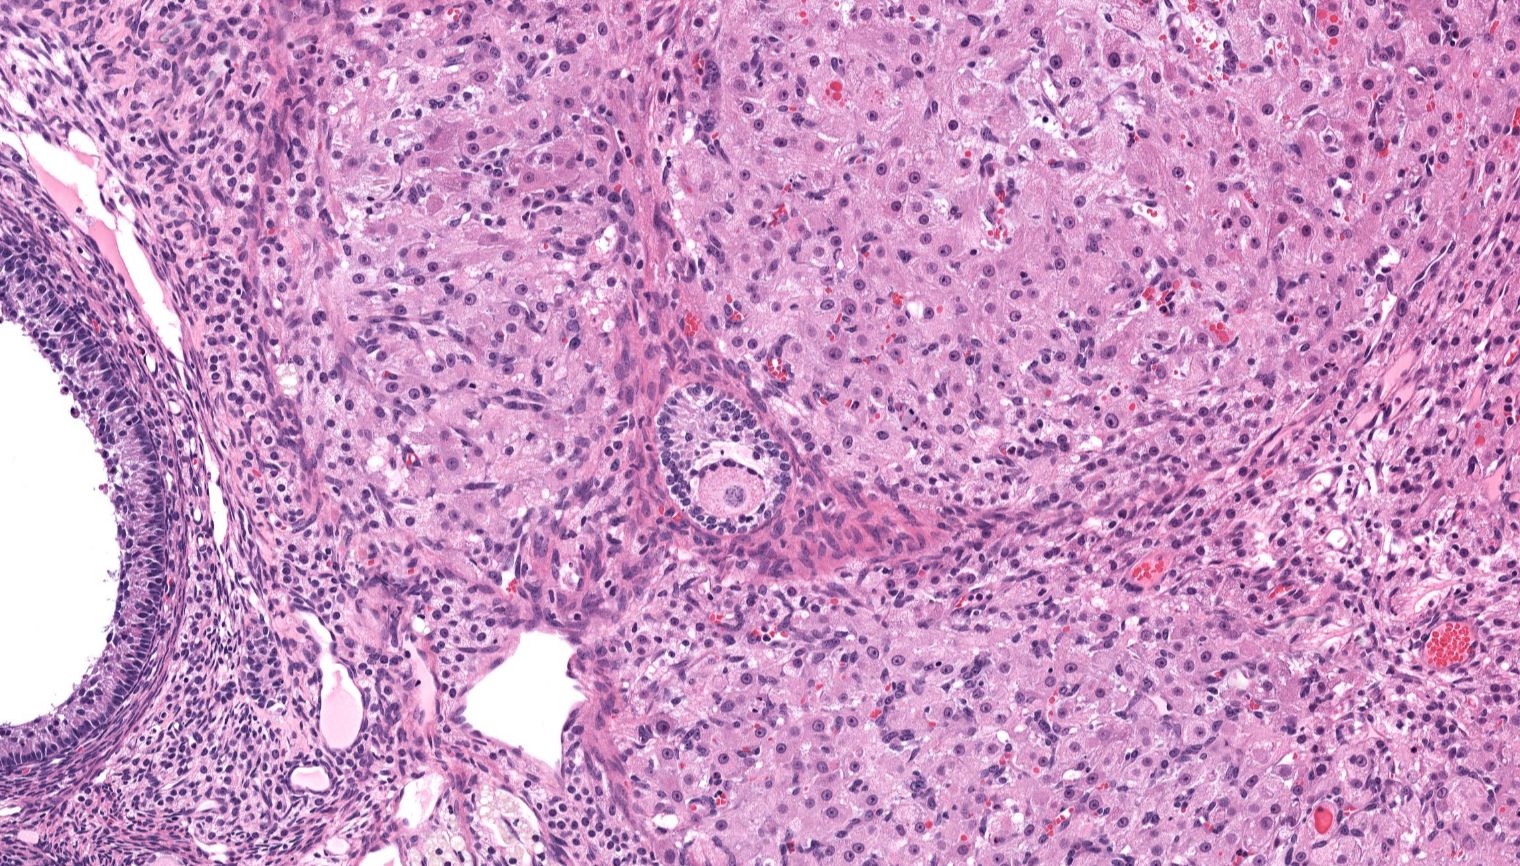

Traditional embryology education often oversimplifies genital system development, relying on binary models that fail to reflect biological diversity. Our interactive module addresses this gap, offering a comprehensive, research-backed exploration of genital development with a focus on inclusivity and scientific accuracy. This approach promotes a deeper understanding of human biology while preparing students for real-world healthcare scenarios that require both medical knowledge and empathy.

Developed over 14 months (September 2023 – November 2024), this project brought together a multidisciplinary team of students, faculty, and medical professionals. Using industry-standard tools such as Adobe Illustrator, Photoshop, Animate, and Articulate 360, we created anatomically accurate visuals and animations. The module follows Universal Design for Learning (UDL) principles and Mayer’s principles of multimedia learning, ensuring an accessible and effective educational experience.

Development of the Genital System